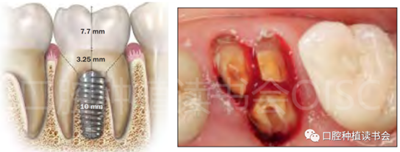

圖1 無法保留的上頜隱裂后牙,拔牙后即刻種植。

后牙區(qū)或者是非美學(xué)區(qū)即刻種植,對(duì)于患者和臨床醫(yī)生而言,存在一些明顯的優(yōu)勢(shì);比如更小的外科創(chuàng)傷、更短的愈合周期、更少的椅旁時(shí)間、更高的患者接受度以及更低的治療費(fèi)用等。除此之外,在上頜后牙區(qū)即刻種植還可以減少上頜竇的氣化現(xiàn)象【Sharan等.2008】;但并非所有的后牙位點(diǎn)都適合即刻種植,后牙區(qū)即刻種植對(duì)醫(yī)生的技術(shù)和經(jīng)驗(yàn)要求更高;由于解剖等諸多條件的差異,美學(xué)區(qū)即刻種植的臨床注意事項(xiàng)與后牙區(qū)即刻種植存在諸多不同之處;與本文旨在通過詳細(xì)的文獻(xiàn)回顧及臨床案例對(duì)后牙區(qū)即刻種植治療提供臨床參考。